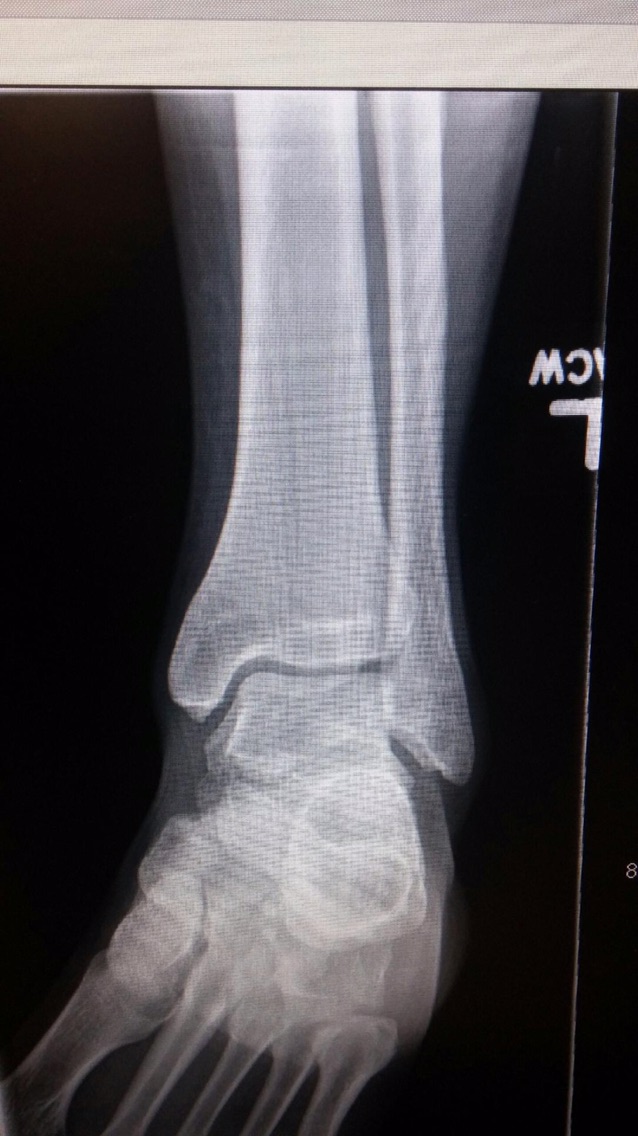

Eventually Jared the guy in charge came back and showed us the X-ray.. gabe has a small break in one of his metatarsals.. much better than a broken ankle..he’ll have to go easy for a couple of weeks.. but no cast or anything.. after how it looked, that seemed like relief. they gave him a support boot to wear and set us up with an orthopedist to see this week.